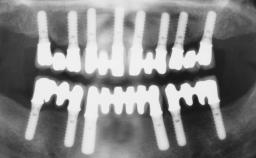

Immediate Loading of Four Implants in the Mandible and Six Implants in the Maxilla and Final Restoration with a Full-Arch Metal Framework FDP and a Full-Arch CAD/CAM Zirconia Framework FDP

# of Implants 10